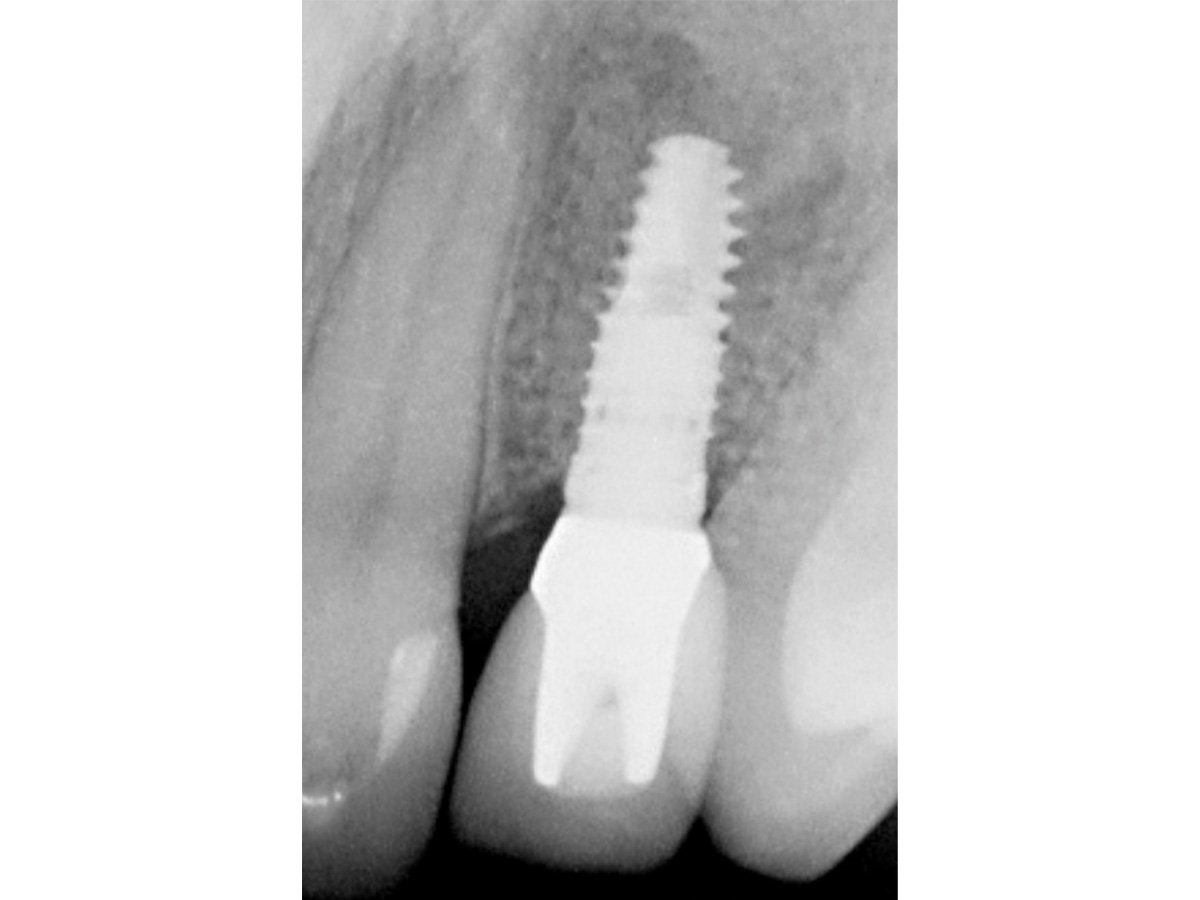

Abbildung 12

Regenerierter Alveolarkamm vor der prothetischen Versorgung.

Abbildung 13

6 Monate nach vollkeramischer Versorgung.

Abbildung 14

6 Monate nach prothetischer Versorgung.

Zu diesem Zeitpunkt kann klinisch und röntgenologisch ein deutlicher Zugewinn von Volumen verzeichnet werden, so dass ein Implantat vom Durchmesser 3,8 mm in der korrekten dreidimensionalen Position eingesetzt werden kann. Mit den beschriebenen augmentativen Maßnahmen konnte ein ästhetisch ansprechendes Gesamtergebnis realisiert werden.